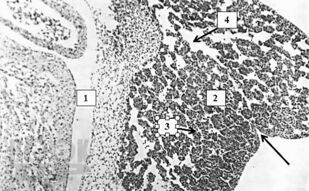

Монография посвящена функциональной морфологии и элементам общей патологии самой большой железы организма человека – печени. Подробно рассматриваются функции, развитие, строение и некоторые виды общей патологии печени, такие, как дистрофии, воспаление, некроз, нарушение кровообращения, склеротические процессы, регенерация и компенсаторно-приспособительные процессы, опухолевые процессы и др. Описываются изменения в печени при шоке, приведены сведения по трансплантации и биоинженерии печени. С учетом самых современных научных данных особое внимание уделяется стволовым клеткам печени и перспективам их использования в терапии печеночной патологии. В монографии широко используются собственные научные данные, причем подробно описаны и проиллюстрированы все стадии развития цирроза печени у лабораторных крыс. Подробно описана оригинальная легковоспроизводимая методика получения цирроза печени у этих животных, обычно представляющая затруднения для воспроизводства. Книга хорошо иллюстрирована высококачественными оригинальными цифровыми микрофотографиями.

В монографии на основе собственных данных проведено сравнение строения печени человека и крыс как в норме, так и при развитии цирротического процесса, что имеет большое значение для фундаментальных исследований. Монография предназначается для гистологов, патологоанатомов, судебных экспертов-гистологов, гепатологов и гепатотрансплантологов, а также магистрантов, аспирантов, преподавателей и студентов всех курсов лечебного и стоматологического факультетов высших медицинских учебных заведений